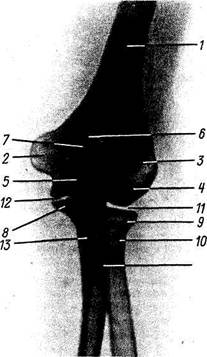

Рис. 44. Рентгенограмма локтевого сустава девочки 9 лет; боковая проекция.

1 — плечевая кость; 2 — локтевая кость; 3 — эпифиз локтевой кости; 4 — эпифизарный хрящ; 5 — лучевая кость; 6 — эпифиз лучевой кости; 7 — эпифизарный хрящ; 8 — суставная щель.

окостенения, возникающих в шести пунктах: в эпифизах (capitulum humeri — на 2-м году, caput radii — на 5 —6-м году, olecranon — на 8 — 11-м году, trochlea — на 9 — 10-м году) и апофизах (epicondylus medialis — на 6 —8-м году и lateralis — на 12 — 13-м году) (рис. 44). В trochlea и olecranon точки окостенения бывают множественными. Поэтому на рентгенограмме области локтевого сустава в детском и юношеском возрасте наблюдается большое число костных фрагментов, наличие которых усложняет дифференциальную диагностику между нормой и патологией. В силу этого знание особенностей окостенения области локтевого сустава является обязательным. К 20 годам наступают синостозы. В случае неслияния костного ядра olecrani с локтевой костью может остаться у взрослого непостоянная кость, os sesamoideum cubiti, или patella cubiti. Окостенение дистальных концов костей предплечья см. с. 131.

Рис. 45. Рентгенограмма локтевого сустава женщины 25 лет; задняя проекция.

Рис. 45. Рентгенограмма локтевого сустава женщины 25 лет; задняя проекция.

1 — диафиз плечевой кости; 2 — медиальный надмыще-лок; 3 — латеральный надмыщелок; 4 — eapitulum humeri; J-блок; 6 - локтевая ямка; 7 — локтевой отросток; § — венечный отросток локтевой кости; 9 — головка лучевой кости; 10 — шейка лучевой кости; //— плечелуче-вой сустав; 12 — плечелоктевой сустав; 13 - диафиз локтевой кости; 14 — бугристость лучевой кости.

На рентгенограммах области локтевого сустава (рис. 45) получается одновременное изображение дистального отдела плечевой кости и проксимальных отделов костей предплечья. На заднем и боковом снимках видны все описанные выше детали этих отделов. На боковом снимке trochlea и capitulum humeri наслаиваются друг на друга, вследствие чего тени этих образований имеют вид концентрических кругов. Хорошо видны «рентгеновские суставные щели» articulatio humeroulnaris, articulatio humeroradialis, art. radioulnaris proximalis.

На задней рентгенограмме особенно ясно заметна щель плечелучевого сустава, на боковом снимке прослеживается на всем протяжении щель плечелоктевого сустава.